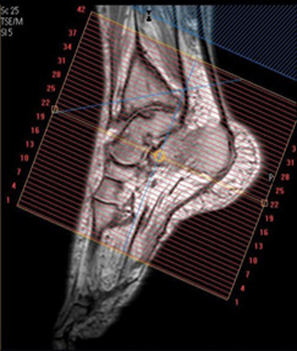

| SAG | T2 STIR | TSE | 3mm | 1mm | STIR | 15cm | Angle to Calcaneus |

| SAG | T1 | TSE | 3mm | 1mm | None | 15cm | Angle to Calcaneus |